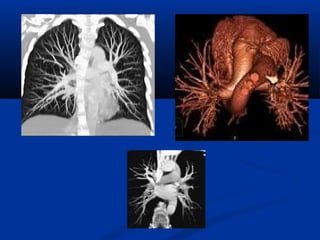

CT ÑA LÔÙP CAÉT (MULTI-SLICE )

-Nhieàu haøng detectors

-Khaûo saùt ñoàng thôøi nhieàu laét

caét

-Thôøi gian queùt nhanh (<0.5

giaây/voøng).

-Khaûo saùt toát trong caùc tröôøng

hôïp caàn thôøi gian nhanh (tim-maïch,

coù bôm caûn quang, boä phaän cöû

Taùi taïo 3DTaùi taïo 3D